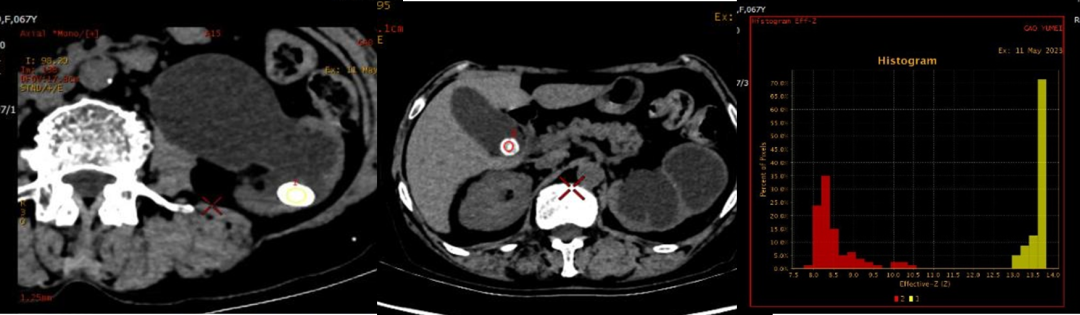

扫描速度快,全身检查只需10秒钟;对于血管性疾病,可发现更细小的血管分支;不受心率、呼吸限制,一次心跳即可完成冠脉CT检查;噪音极小;单能量成像,更加准确的绝对CT值;低KeV成像,更高的组织对比度;多参数功能成像,可进行多种基物质浓度及有效原子序数测定。

3.有效原子序数通过计算有效原子序数,可进行物质的检测、鉴别及分离,临床用于结石成分、痛风成分分析等。

4.能谱曲线:临床中可用于组织同源性检查、病灶的鉴别诊断、组织定性与定量、绘制曲线斜率等。